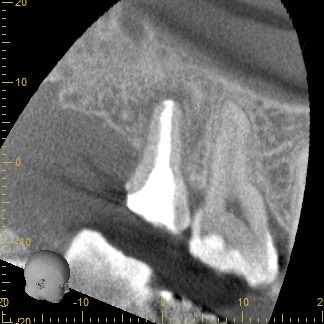

歯根周囲の骨の吸収が大きく、保存が可能かどうか判断が難しいと思われたCT画像

従来のレントゲン画像は全てのものが影絵として一枚の平面に写し出されるため、根の先の病巣の大きさを詳しく調べることが困難です。そこで、CT撮影を行うことで、3次元的に様々な角度で確認し、根の先の病巣がどれほどの大きさを調べその歯が保存可能なのかどうかを診ていきます。

この写真は術前のCT画像です。

歯根の周囲に見られる黒くなっている部分は、細菌の感染により骨が吸収しています。根尖病巣と呼ばれるこの部分が大きいほど治る確率が下がると言われ、根管内の細菌数も多いことがほとんどです。

ここまでの吸収があると、歯根が破折してる可能性を考える必要があります。